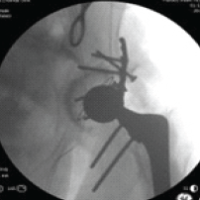

A 24-year-old male sustained a high-energy injury with multiple pelvic fractures in addition to a displaced Garden’s type IV, Pauwel’s type III femoral neck fracture. Mild traction and valgus fixation with compression were achieved using the FNS, with adequate positioning of the blade and anti-rotation screw and bi-cortical distal locking. The patient was lost to follow-up as he was a native of West Bengal. However, we established contact with the patient after 12 months and his latest X-Rays showed that the fracture had united, but by 16 months AVN of the femoral head with secondary degenerative changes developed (Fig. 3). The displacement, comminution, high-energy mechanism, and possible early return to weight-bearing may have contributed to this complication, despite good implant placement and good bone quality.

Figure 3: (Case 4) Top right: Pre-operative 3D computed tomography image showing supero-postero-lateral neck comminution; Centre-right: Immediate post-operative AP radiograph; bottom row: intraoperative C-arm images; Top left: 16 months post-operative radiographs showing fracture union and osteoarthritis hip changes secondary to AVN